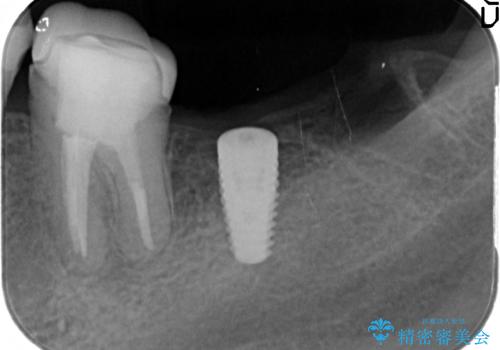

最後方臼歯のインプラント補綴

- 矯正治療・銀歯のやりかえ希望で来院されました。

矯正治療により歯並びの改善を行いつつ失われた最後方臼歯をインプラントを用いて咬合機能回復します。

- 40万円(ストローマンインプラント・カスタムチタンアバットメント・メタルボンドクラウン)費用は治療当時の料金となります

最後方臼歯を喪失した場合、入れ歯・インプラントによる咬合機能回復方法があります。

今回はしっかりと噛むことができ、取り外しの必要のないインプラントによる補綴を行いました。